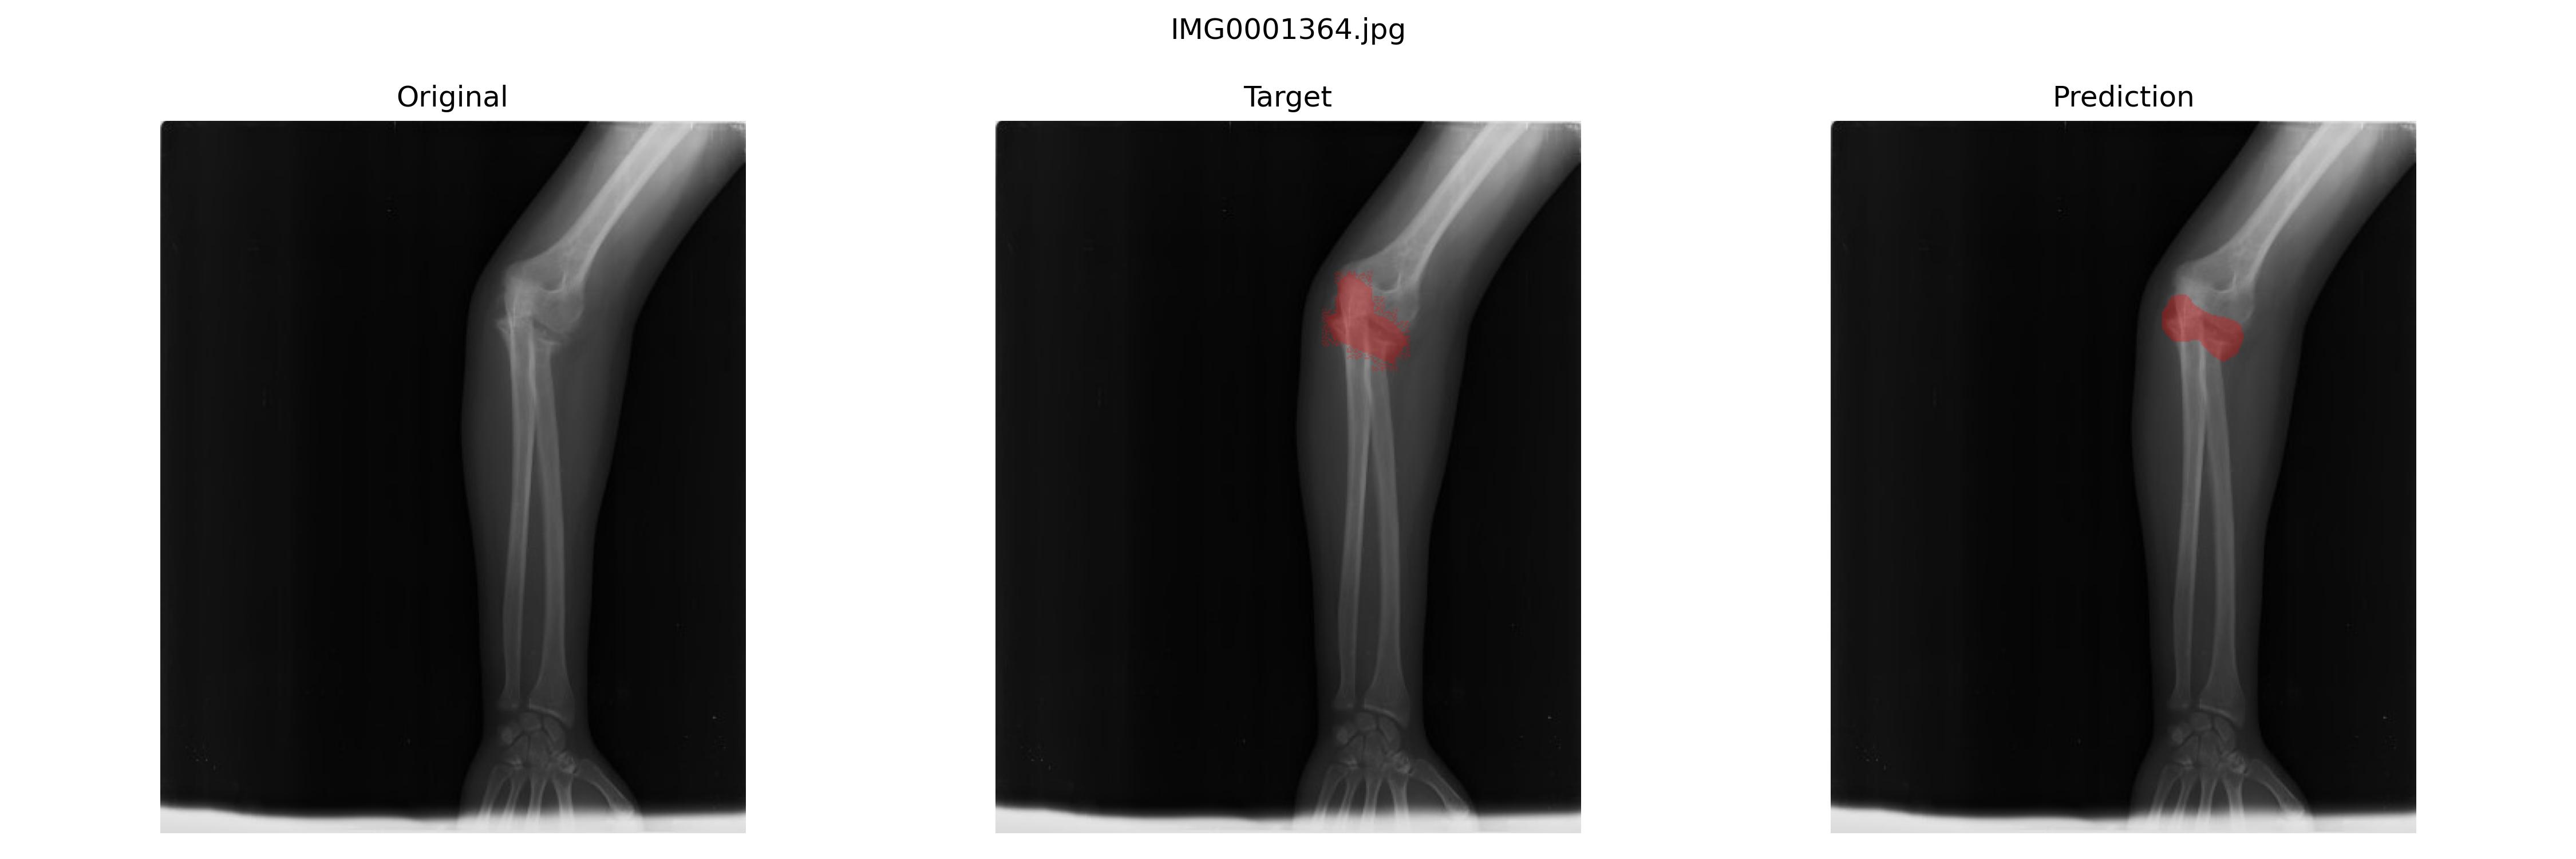

最佳模型是

epoch:110,sensitivity(Recall):0.3831927899240895,specificity:0.9985073638473289,precision:0.6006053270923088

好的结果

不好的结果

最后结果并不是很好,并且换了U-net以及加权交叉熵损失、Dice损失之类的之后也一样,我认为和这个数据集的标注逻辑有关。骨折的地方就那个断面,周围标注可大可小,这种应该比较适合bbox标注做目标检测。